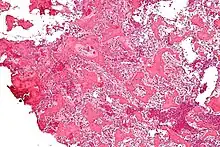

Histological findings

On histological examination, osteoid osteoma consists of a small (< 1.5–2 cm), yellowish-to-red nidus of osteoid and woven bone with interconnected trabeculae, and a background and rim of highly vascularized, fibrous connective tissue. Varying degrees of sclerotic bone reaction may surround the lesion. Benign osteoblastoma is virtually indistinguishable from osteoid osteoma. The usual appearance included a fibrovascular stroma with numerous osteoblasts, osteoid tissue, well-formed woven bone, and giant cells. The osteoblasts were generally small and regular in shape.[7]